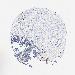

OVARIAN CANCER - Protein expressioni

A mouse-over function shows sample information and annotation data. Click on an image to view it in a full screen mode. Samples can be filtered based on level of antibody staining by selecting one or several of the following categories: high, medium, low and not detected. The assay and annotation is described here.

Note that samples used for immunohistochemistry by the Human Protein Atlas do not correspond to samples in the TCGA dataset.

Antibody stainingi

Antibody staining in the annotated cell types in the current human tissue is reported as not detected, low, medium, or high, based on conventional immunohistochemistry profiling in selected tissues. This score is based on the combination of the staining intensity and fraction of stained cells.

Each image is clickable and will lead to virtual microscopy that enables deeper exploration of all samples and also displays staining intensity scores, fraction scores and subcellular localization as well as patient and tissue information for each sample.

Antibody HPA003134

Cystadenocarcinoma, mucinous, NOS

Carcinoma, endometroid

Cystadenocarcinoma, serous, NOS